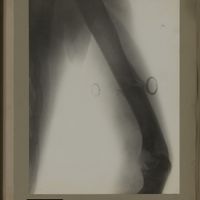

0120 - Page 8 - [Radiographie de l'humérus]0120 - Page 8 - [Radiographie de l'humérus]

0127 - Page 15 - [Radiographie de l'humérus et du thorax]0127 - Page 15 - [Radiographie de l'humérus et du thorax]